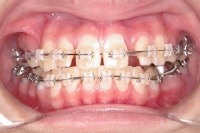

上顎の外側にセラミックブラケットを装着

下顎の奥歯にバンドを装着

下顎の外側にセラミックブラケットを装着